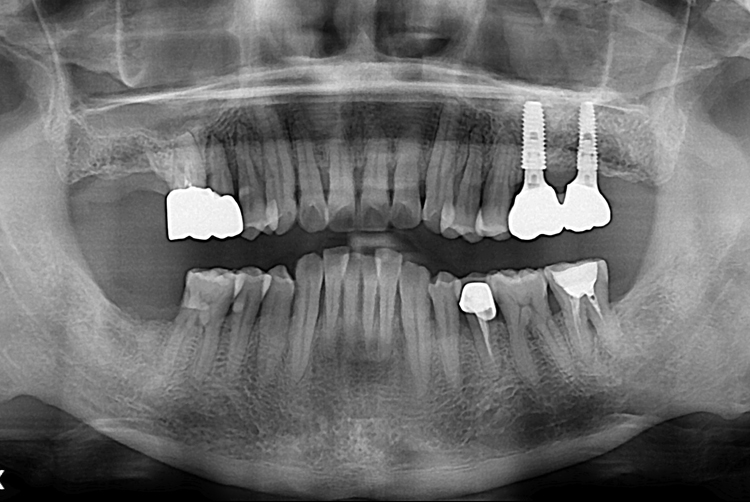

[임플란트] 어금니 임플란트

치료전 : 2017-06-13

세종치과는 많은 환자와 다양한 케이스를 바탕으로

항상 편안한 임플란트 수술을 제공하고자 노력하고,

오래동안 튼튼히 쓸 수 있는 임플란트 수술을 가장 큰 목표로 삼고 있습니다.